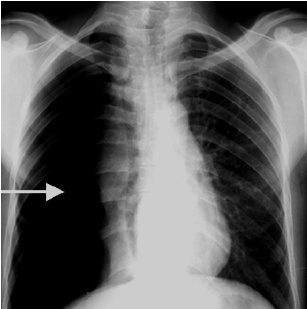

解題:箭頭所指部分漆黑一片,根據公式得出氣胸